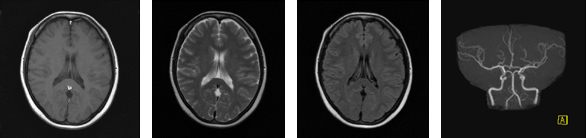

○頭部